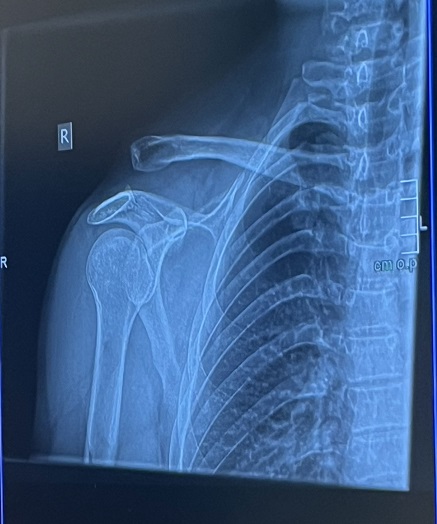

Ursprünglich hatte ich geplant, im Sommer mit meiner Familie den ersten Urlaub in unserem neuen Camper zu verbringen. Leider kam es anders, da ich mich beim Downhill-Fahren verletzt habe. Ich habe mir mehrere Bänder in der Schulter gerissen, was eine Operation notwendig machte und mich seitdem stark einschränkt.

Derzeit kann ich leider keine Sport- oder Freizeitaktivitäten ausüben, die meine Schulter belasten – und das schließt fast alles ein, was ich gerne draußen mache.